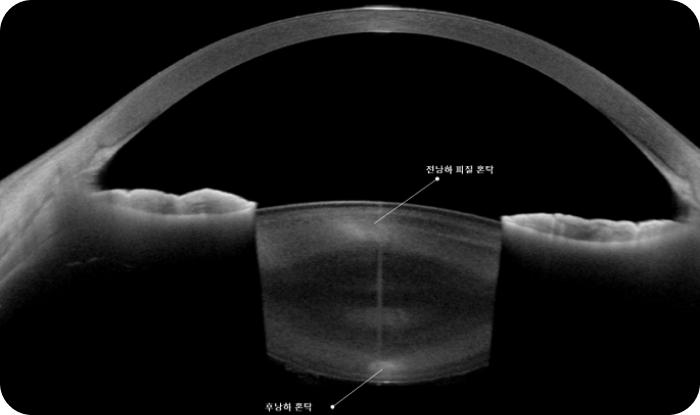

후낭하 백내장 증례 사진

<그림> CT 소견으로 보는 후낭하백내장

수정체의 후극부에만 혼탁이 존재하기 때문에 동공이 작은 환자분들은 세극등현미경 검사 만으로는 수정체 혼탁을 발견하기 쉽지 않지만,

CASIA2 고해상도 CT를 이용하면 놓치지 않고 그것도 아주 손쉽게 진단 가능합니다.